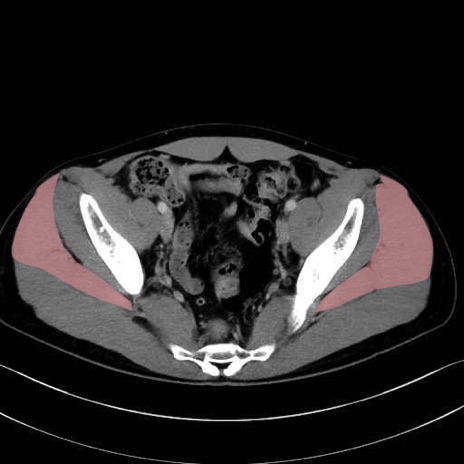

中殿筋 (Gluteus medius)